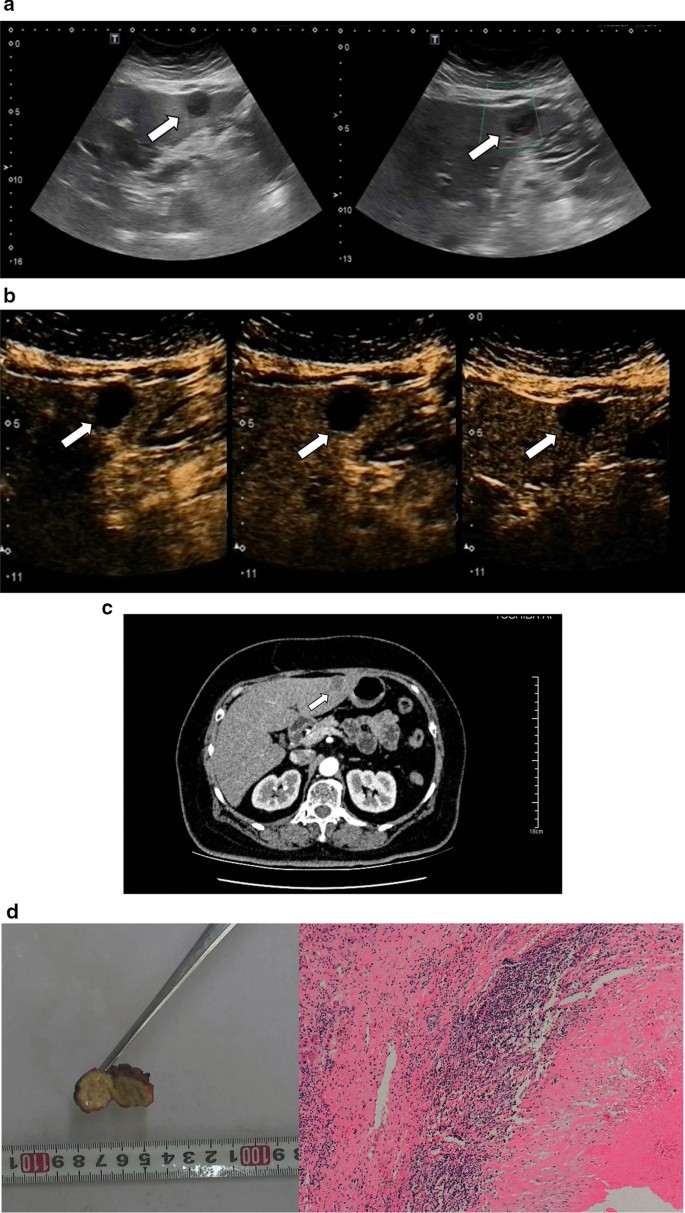

Images in a 50–60-year-old sex "1" with a history of hepatocellular carcinoma 3 years after surgery. a There was a hypo-echoic lesion in segment 4 of the liver with a size of 3.0 cm × 2.5 cm. Normal hepatic blood vessels could be seen around the lesions but no obvious blood flow signal was detected. b In arterial phase (timer, 00: 13), the lesions showed obvious thin peripheral rim-like enhancement, and the thickness of the enhanced ring was 0.36 cm; this demonstrated iso-enhancement in the portal phase (timer, 01: 29) and delayed phase (timer, 04:10). There was no contrast agent filling in the interior of the lesions. c Enhanced computed tomography showed no obvious enhancement in the lesions but enhancement in the boundary of the lesion. d Necrotic tissue of the surrounding liver tissue and focal inflammatory cell infiltration could be seen (hematoxylin and eosin, × 100)

Images in a 40–50-year-old sex "2". a There were two hypo-echoic lesions in segment 7 of the liver which connected like a dumbbell. Normal hepatic blood vessels could be seen inside (the lesions connected portion) and around the lesions. b In the arterial phase (timer, 00:24), the lesions showed thin peripheral rim-like enhancement, and the thickness of the enhanced ring was 0.23 cm; this showed iso-enhancement in the portal phase (timer, 00: 57) and delayed phase (timer, 02: 03). There was no contrast agent filling in the interior of the lesions. c Enhanced CT showed no obvious enhancement in the lesions but showed enhanced blood vessels. d A large area of necrotic tissue with surrounding inflammatory cell infiltration could be seen (hematoxylin and eosin, × 100)